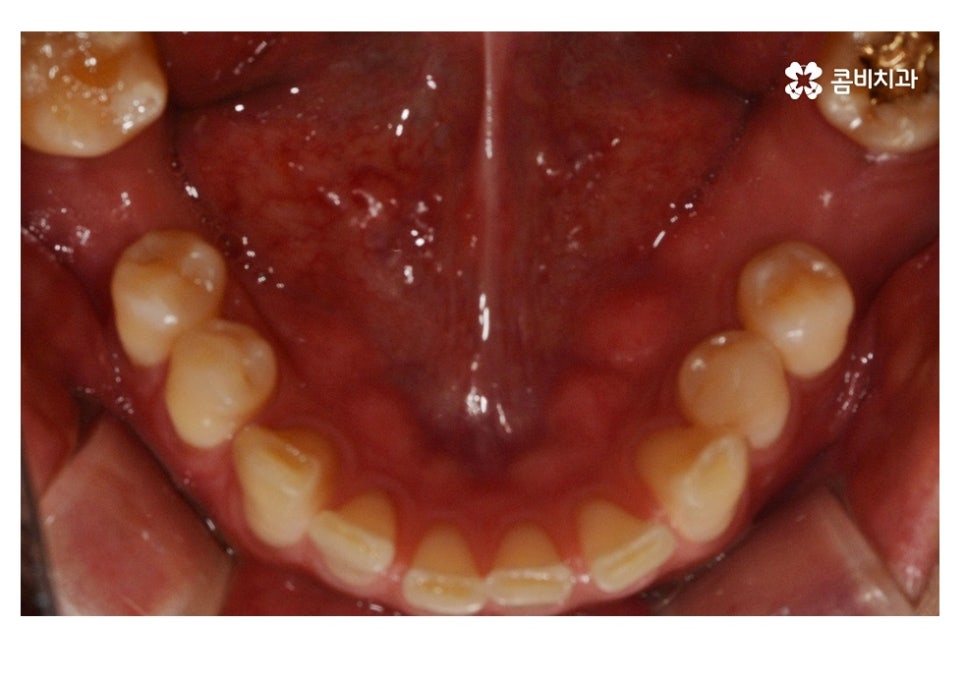

위 사례 이미지에서 보시는 것과 같이 불규칙한 치열 외에도

치아 사이가 벌어져 있으면 심미성 뿐 아니라

음식물이 치아 사이에 끼기 쉽기 때문에 충치, 잇몸질환이

발생하기 쉬울 수 있어요.